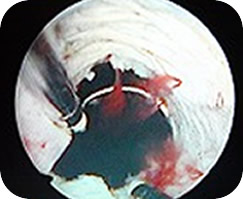

全経過 つい、忙しさにかまけて。orz 尿切れの悪さ(5年程前から)頻尿気味(1年程前から)を放置してたら血尿が出た(08年2月中旬)。まだ軽く考えてたら「膀胱ガンってこともある」と言われ、急いで枚方市民病院へ。一般的な検査+エコー検査・CTスキャン・尿道からファイバースコープ等の結果、前立腺に「腫瘍のようなもの」が見つかる。手術前検査の時点では「前立腺癌の疑い」。08年3月19日に経尿道的前立腺切除術(膀胱鏡手術器を尿道より挿入し、尿道の閉塞原因の前立腺肥大症を電気メスで削る)を受ける。結果的に今回は悪性じゃなくて良性腫瘍と前立腺肥大だった。 ★前立腺肥大は投薬や注射で治療することもあるので肥大イコール手術という訳ではありません。50歳代の男性の約半数が肥大傾向で、日常生活に問題がなければ特に治療は必要ないといいます。ただし私のように血尿となると他の病気の可能性も出てくるのでぜひ受診を!

ハイテク手術。ハロー、尿道。 正直、すごい世界です。

手術前は大いに緊張したものの、実際始まってみると暖かい部屋で音楽を聞きつつモニタを見ながらの手術。なんてハイテク。メスも使わず全身麻酔じゃないので意識はあるが痛みは全くナシ。その上このモニタ映像はDVDでお土産にもらえるし・・・なんだかSM。ちがったSF。